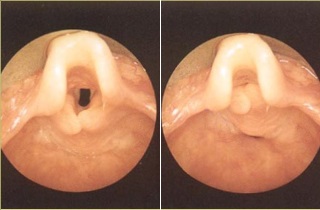

У некоторых людей могут быть индивидуальные анатомические особенности, при которых передняя поверхность надгортанника частично сворачивается. Это затрудняет доступ к гортани и усложняет проведение непрямой ларингоскопии.